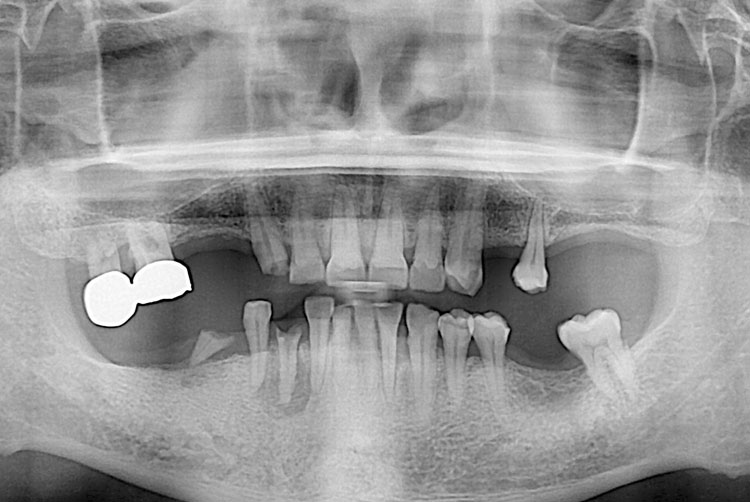

[임플란트] 임플란트

치료전 : 2016-02-17

치료후 : 2020-01-08

세종치과는 많은 환자와 다양한 케이스를 바탕으로 항상 편안한 임플란트 수술을 제공하고자 노력하고,

오래동안 튼튼히 쓸 수 있는 임플란트 수술을 가장 큰 목표로 삼고 있습니다